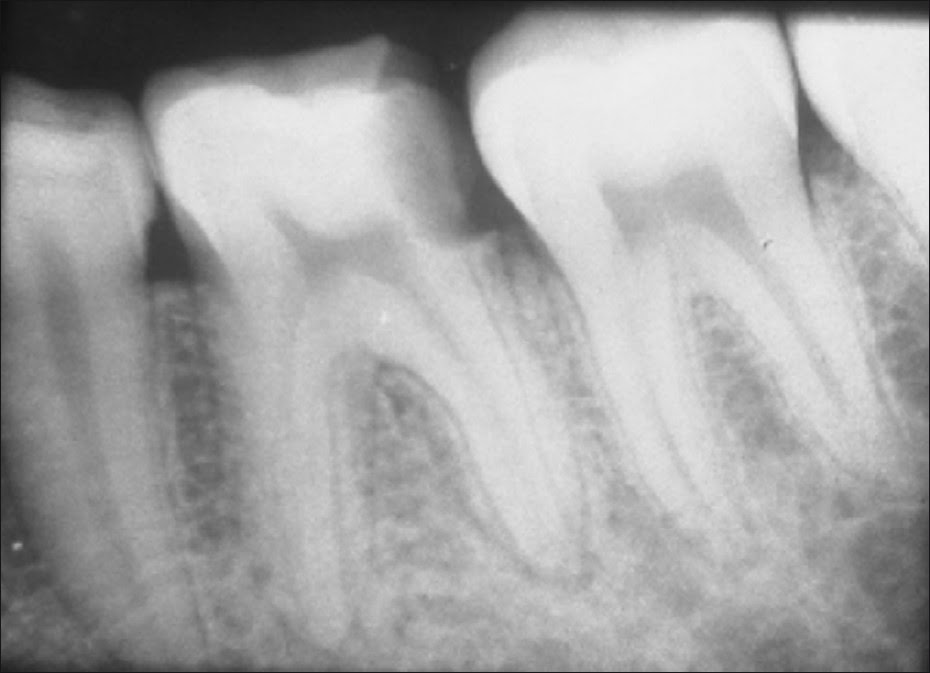

Конкрементозный пульпит: симптомы и методы лечения

Раздел: Снимки мастерства